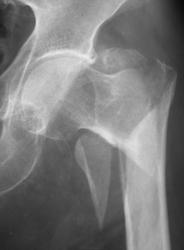

Чрезвертельный с отрывом малого вертела, смещением бедренной кости кверху и кнаружи.

И кажется не свежий

С переломом все ясно, согласна с коллегами. А структура головки по нижнему контуру не смущает?

Ну кажется, что это кистовидная перестройка, да ещё и обезыствление стенок артерии

Оскольчатый чрезвертельный со смещением и уменьшением шеечно-диафизарного угла. Боковой снимок?

Смущает. Асептический некроз головки?